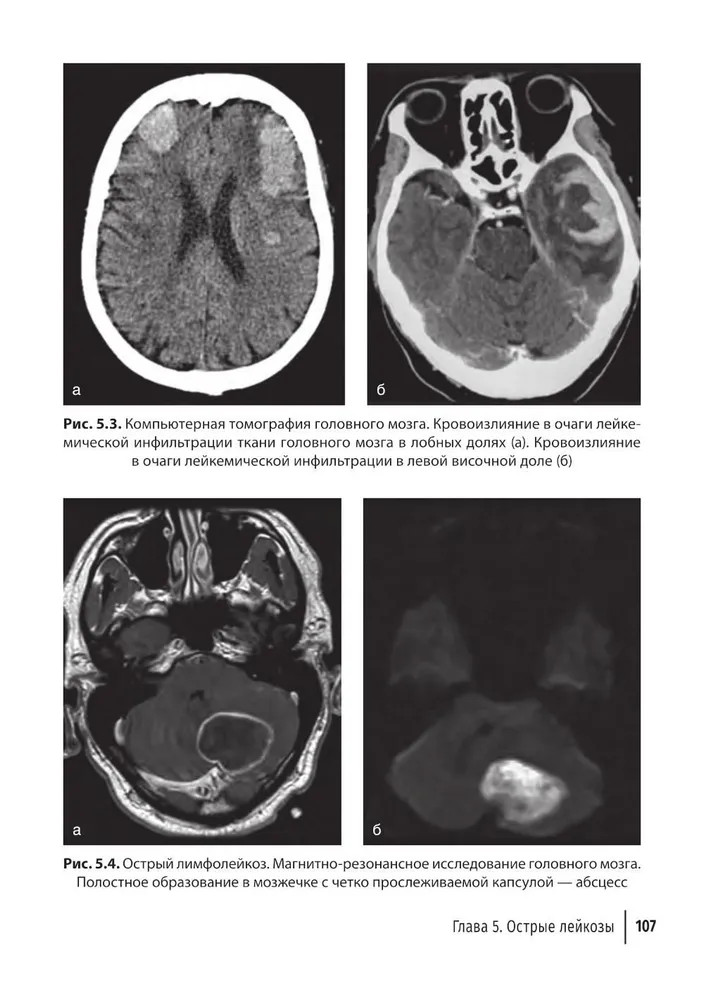

💳 Оплатить за товар можно при получении 🇰🇿 Есть бесплатная доставка по Казахстану 🎁 Копите бонусы с каждой покупки В руководстве представлен широкий спектр сведений, касающихся лучевой диагностики заболеваний системы крови. Охарактеризованы патологические изменения органов и тканей, выявляемые всеми доступными методами лучевой диагностики. Это классическое рентгеновское исследование, ультразвуковое исследование, компьютерная томография, магнитно-резонансная томография и позитронно-эмиссионная томография. Наиболее подробно освещены заболевания, относящиеся к гемобластозам (лейкемии, лимфомы, множественная миелома), также уделено внимание незлокачественным болезням (анемии). Издание содержит большое количество иллюстраций. Информация четко структурирована, что делает удобным использование руководства в качестве справочного пособия. При создании руководства основной акцент был сделан на его полезности в повседневной практической работе. Издание адресовано врачам-гематологам, рентгенологам, онкологам и врачам других специальностей, а также может быть использовано при обучении студентов, аспирантов, ординаторов и слушателей сертификационных курсов и курсов повышения квалификации. |